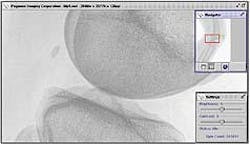

FIGURE 1. Using wavelet compression, a server stores a minimum-resolution image and compresses the additional data using a wavelet transform. The server then sends the minimum-resolution picture immediately and fills in the picture over time until either the user decides on an acceptable resolution or receives the entire image file. In the knee x-ray, the small thumbnail (far right), indicates the region of interest. The Pegasus software requests coefficients for pixels in the region of interest and then fills in the additional details outside the region of interest.